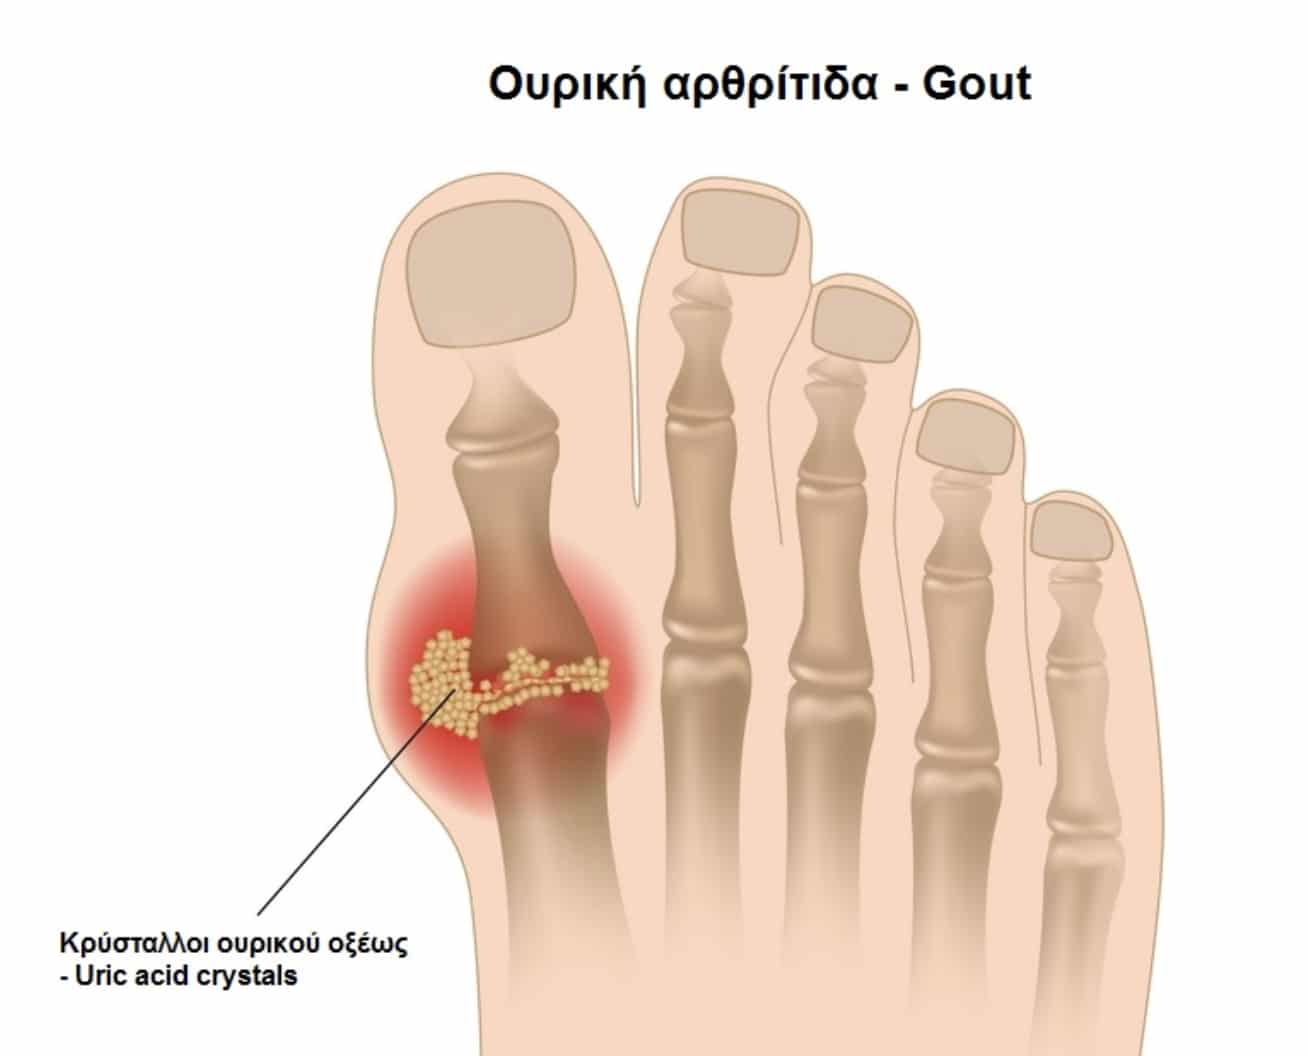

Ουρική ή Ψευδοουρική Αρθρίτιδα

Ένα ξαφνικό, έντονα επώδυνο πρήξιμο στο ένα γόνατο μπορεί να οφείλεται σε ουρική αρθρίτιδα, που προκαλείται από τη συσσώρευση κρυστάλλων ουρικού οξέος στην άρθρωση. Μια παρόμοια πάθηση, η ψευδοουρική αρθρίτιδα, περιλαμβάνει κρυστάλλους ασβεστίου. Συνήθως επηρεάζουν μόνο μία άρθρωση κάθε φορά και εκδηλώνονται ξαφνικά.